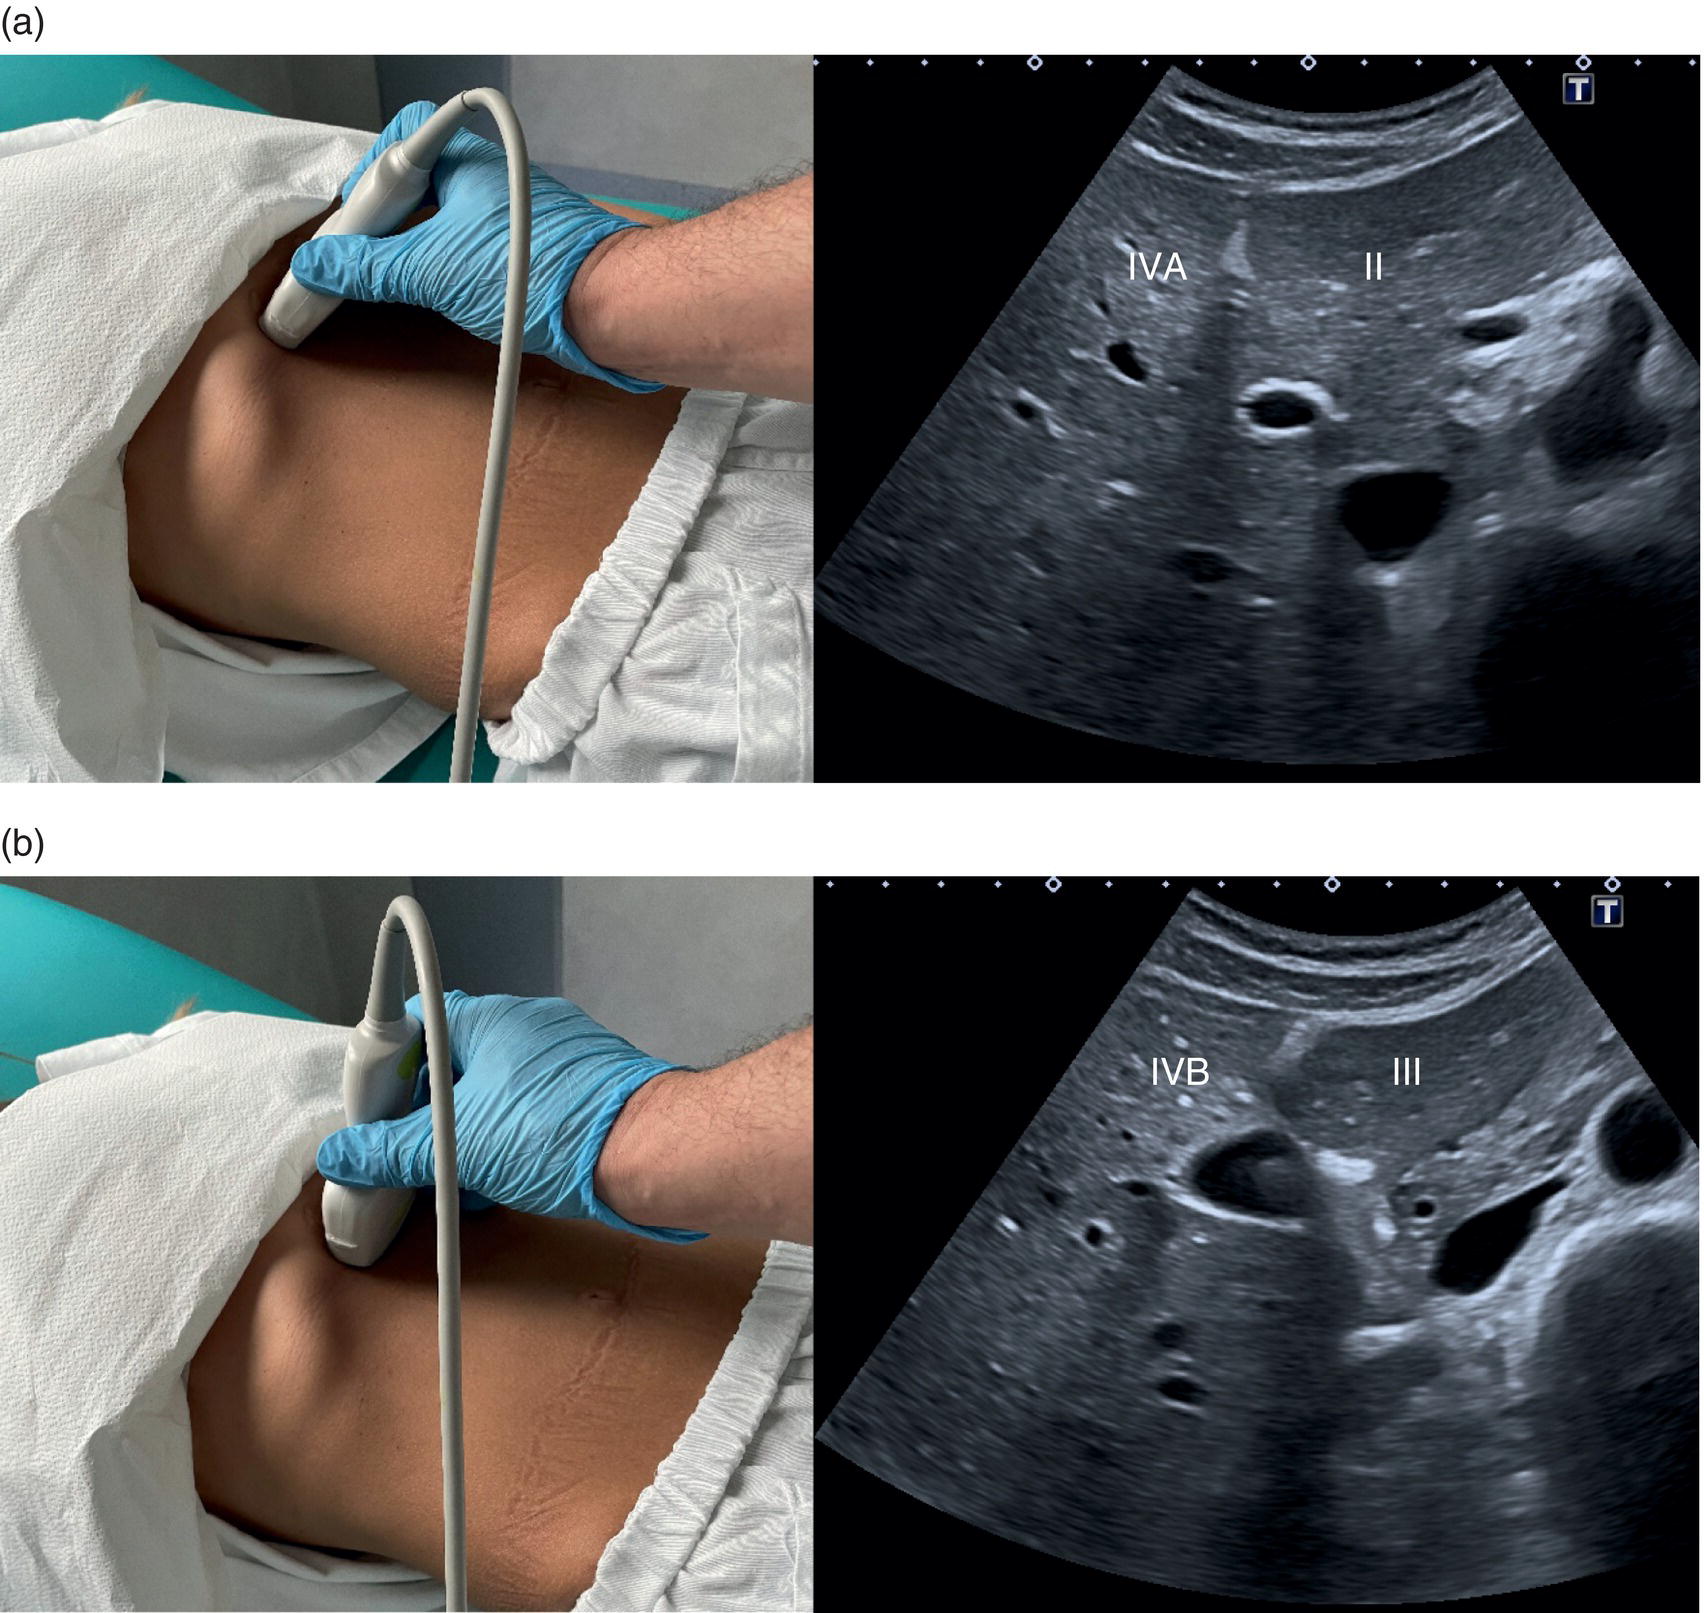

Next, bearing in mind that the LHV represents the boundary between segments II/III and IV, turn the probe into the transverse scan (TS) plane and then sweep up and down, ensuring that these liver segments are also visualised in the orthogonal plane. By doing so segment IVA will be visualised in the most cranial plane next to segment II, and segment IVB will be visualised just below, next to segment III (Figure 3.22). Segment IV should also be imaged in LS view (Figures 3.21 and 3.23) (Videos 3.2 and 3.3). Be aware of the appearance of the ligamentum teres in the TS plane, since it may mimic a hyperechoic focal lesion, and keep in mind that all structures need to be visualised in at least two planes (Figure 3.5) (Video 3.4). ![]()

Based on the divisions of the portal and hepatic veins, the liver may be divided into eight segments, as first suggested by the French surgeon Claude Couinaud in 1957 (Figure 3.14) [4]. This classification relies on the fact that each of these segments has its own individual blood supply and might be resected without jeopardising the viability of other segments. In this classification, the liver segments II and III are situated to the left of the LHV and falciform ligament, and the left branch of the PV (LPV) divides them into segment II (above the PV) and segment III (below the LPV). Segment IV is situated between the LHV and the MHV and the LPV divides them into segment IVA (above the LPV) and segment IVB (below the LPV). Segments V and VIII are located between the MHV and RHV, whereas segments VI and VII represent most lateral segments situated to the right of the RHV. The right branch of the RPV divides segment V (caudal) from VIII (cranial) and segment VI (caudal) from VII (cranial) (Figure 3.15). On the dorsal, central part of the liver, between the IVC and the venous ligament, lies the caudate lobe that corresponds to segment I (Figures 3.6 and 3.12c).